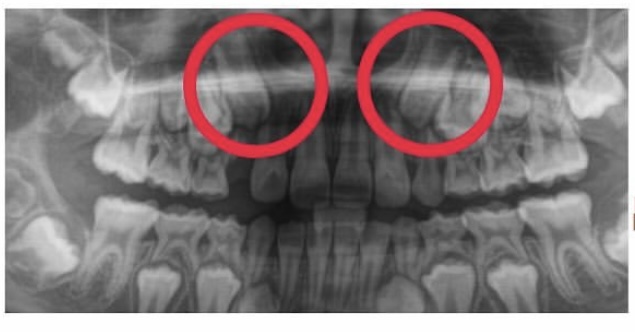

次に生え変わるのは…

次の生え変わりは3番目の歯です。

この歯は根っこが長く、よく八重歯と呼ばれ、外側が出ているような歯になることが多いです。

実際に生えてくるとこのように大きい歯が出てきます。

幅が足りずこのままでは八重歯になってしまいそうでした。